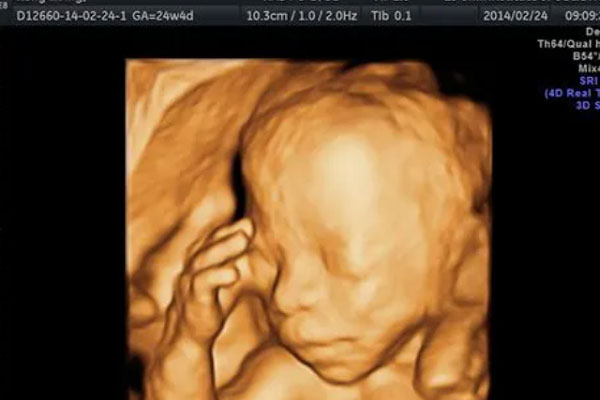

B超四维一看面相就是男孩?附男宝脸型参照图

四维B超主要就是用来排畸的,在22-24周左右检查,因为这个时候胎儿的肢体及各主要脏器已经全部发育,而且羊水较适合做胎儿畸形筛查。但是民间流传从四维彩超图片看胎儿的面..